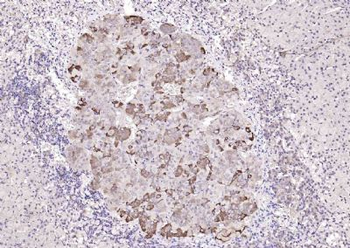

50 μl, 100 μl, 200 μlAnti-Aurora A/AURKA Antibody [orb1290027]

ELISA, FC, IHC, WB

Human

Rabbit

Polyclonal

Unconjugated

10 μg, 100 μgChemerin Rabbit Polyclonal Antibody [orb156351]